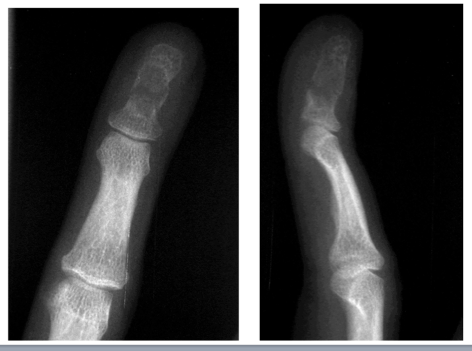

Endochondroma

What is this?

Lobules of hyaline cartilage with minimal atypia (no bone formation)